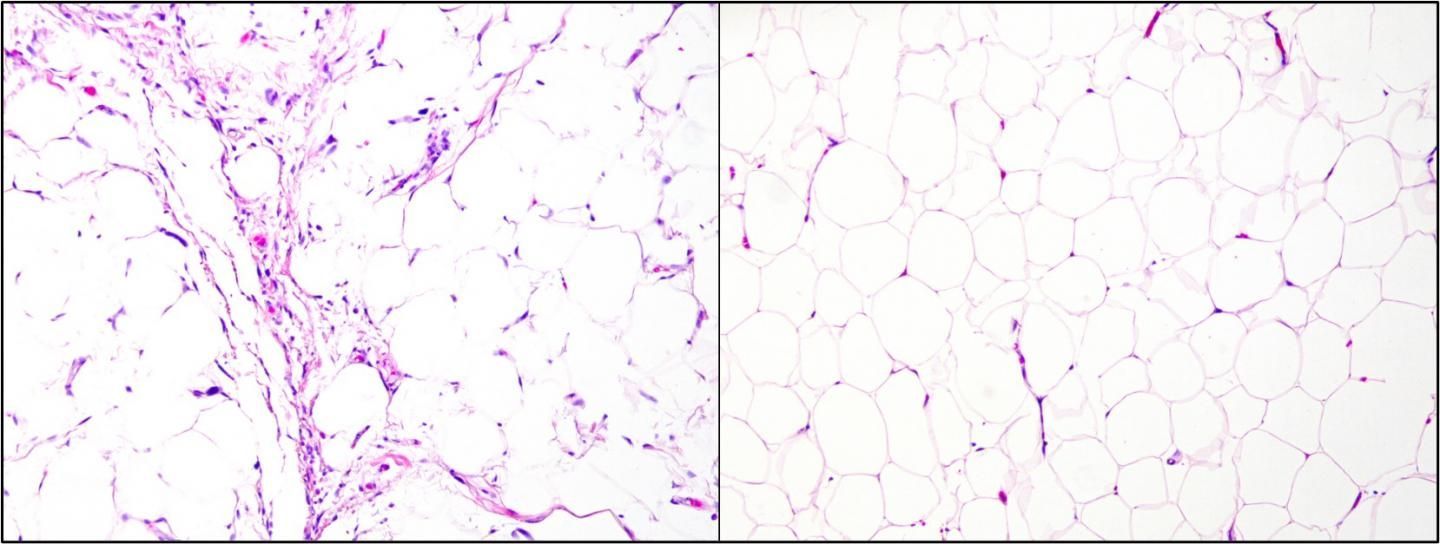

"Liposarcomas are a type of malignant cancer that is difficult to diagnose because, even under a microscope, it is hard to differentiate liposarcomas from benign tumors or other types of cancer that need different treatments," explains lead investigator Torsten Owen Nielsen, MD, PhD, Genetic Pathology Evaluation Centre, Department of Pathology and Laboratory Medicine, University of British Columbia, Vancouver, Canada. "Many liposarcomas look like their benign and relatively common counterparts, lipomas. Diagnostic delay and uncertainty cause severe stress for patients, and misdiagnosis can have many consequences including delayed or inadequate treatment or unnecessary surgical procedures and long-term postoperative follow up."